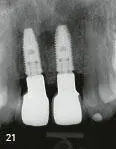

Figs 219 to 221 Vertical augmentation of the anterior maxilla - фото 76 Figs 219 to 221 Vertical augmentation of the anterior maxilla cont - фото 77 Figs 219 to 221 Vertical augmentation of the anterior maxilla cont - фото 78

Figs 2-19 to 2-21 Vertical augmentation of the anterior maxilla (cont).